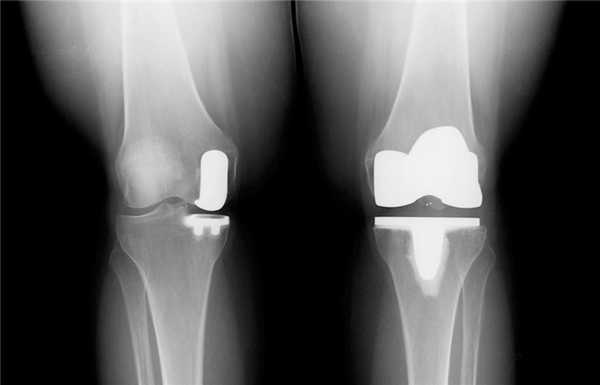

Одномыщелковая замена сустава на рентгене.

Две техники операции у одного пациента.